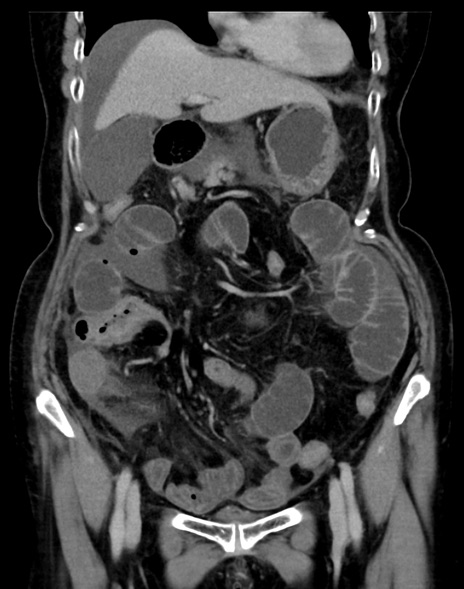

症例13 CT(冠状断像)1日半後